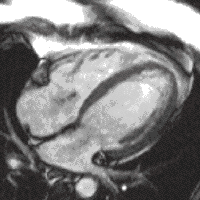

A 4 chamber view of the heart using SSFP cine imaging. Compare the image orientation (4 chamber) with the short axis view of the movie above